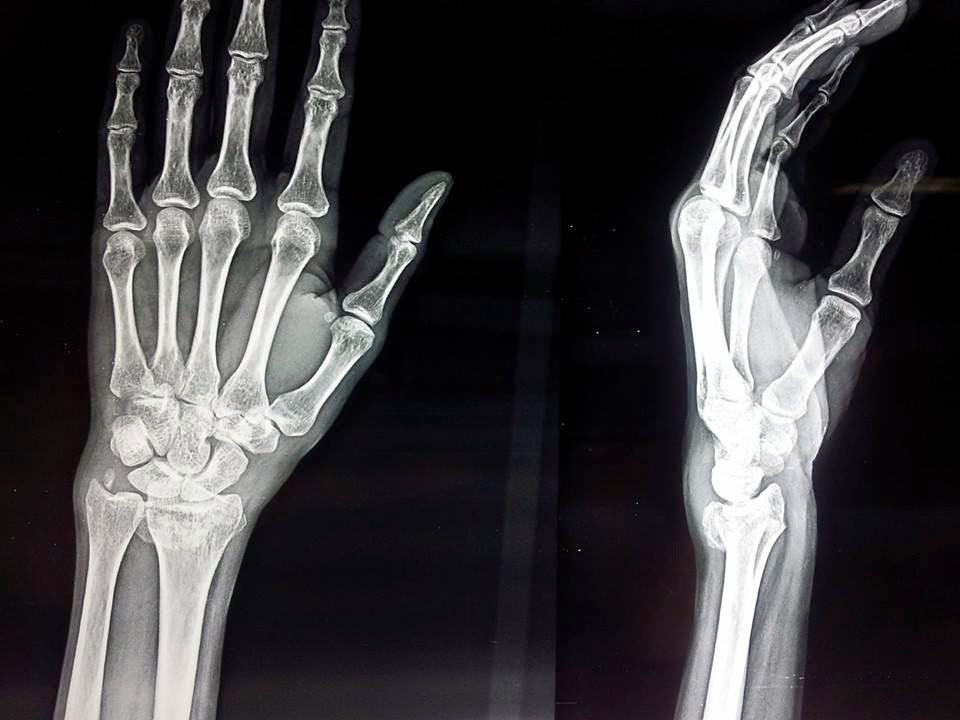

In this era of universal plating, I still prefer K-wires for simple distal radius metaphyseal fractures, particularly in young patients (low risk of stiffness) and non-dominant extremity (less interference with ADL).

Anuj Agrawal Alind Kishore Singh There is no dorsal angulation. Will post a clearer x-ray after removal of cast.